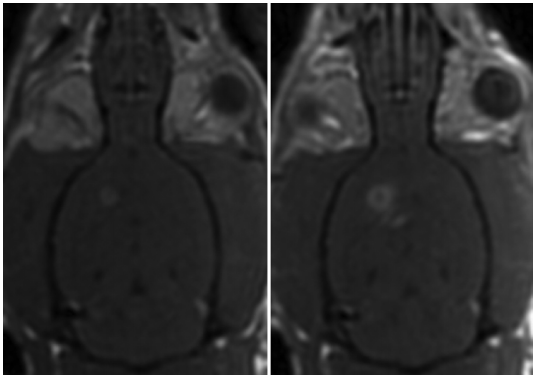

图2所示。磁共振成像引导下FUS损害脑肿瘤移植物周围的血脑屏障。冠状面钆增强t1加权磁共振图像的大鼠脑前(左)和后(右)超声。超声证实的右半球周围肿瘤超声增强增强。无回声的左半球缺乏对比度增强。